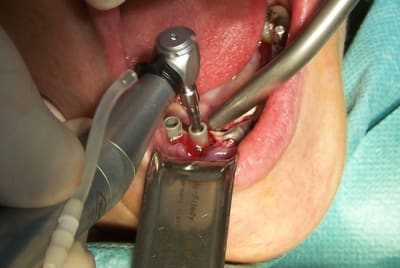

Ce cas est limite et aurait pu être traité en deux temps mais bon, j'ai opté pour y aller franco...

La seamine prochaine je vous montrerai la finition céramique.

Bon la suite des photos mais il faut commencer par la dernière, l'ordre de passage lors de l'envoi s'est apparemment inversé...

Zut, l'ordre des photos n'est pas celui que j'avais prévu, vous voudrez bien remettre dams l'ordre en lisant les titres. Le logiciel d'eugénol mélange tout à sa guise...